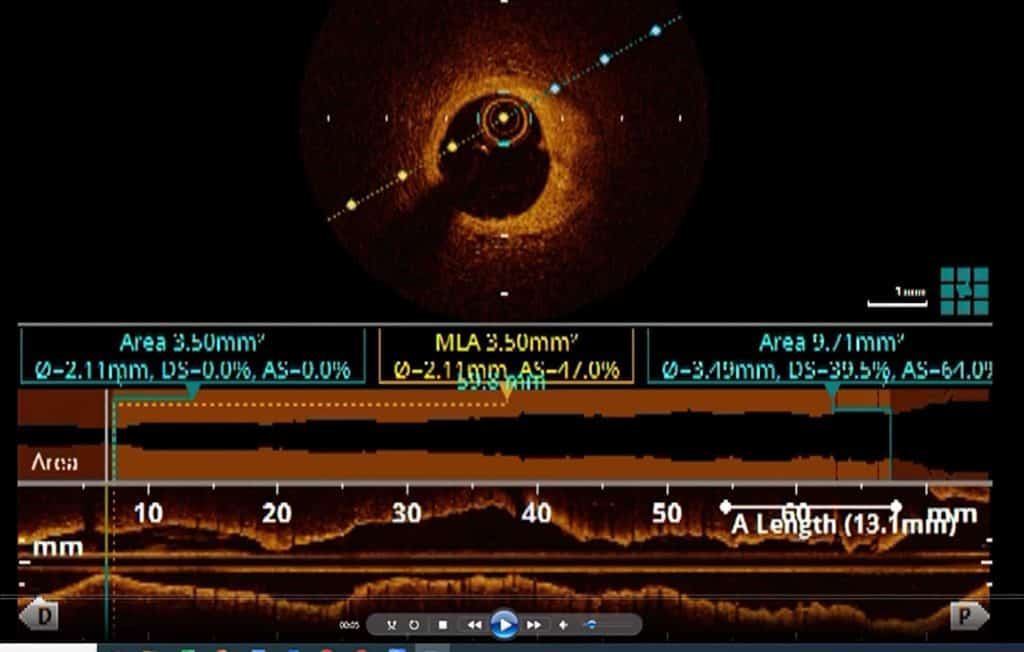

Modalitas tambahan yang dapat digunakan untuk menilai arteri koroner lebih lanjut

Cadangan Aliran Pecahan (FFR)

This is used to assess the degree of pressure-flow difference after and before the stenotic part of the coronary artery.

A fine flexible catheter with a pressure-measuring sensor is threaded through the blockage and pressure readings are taken.